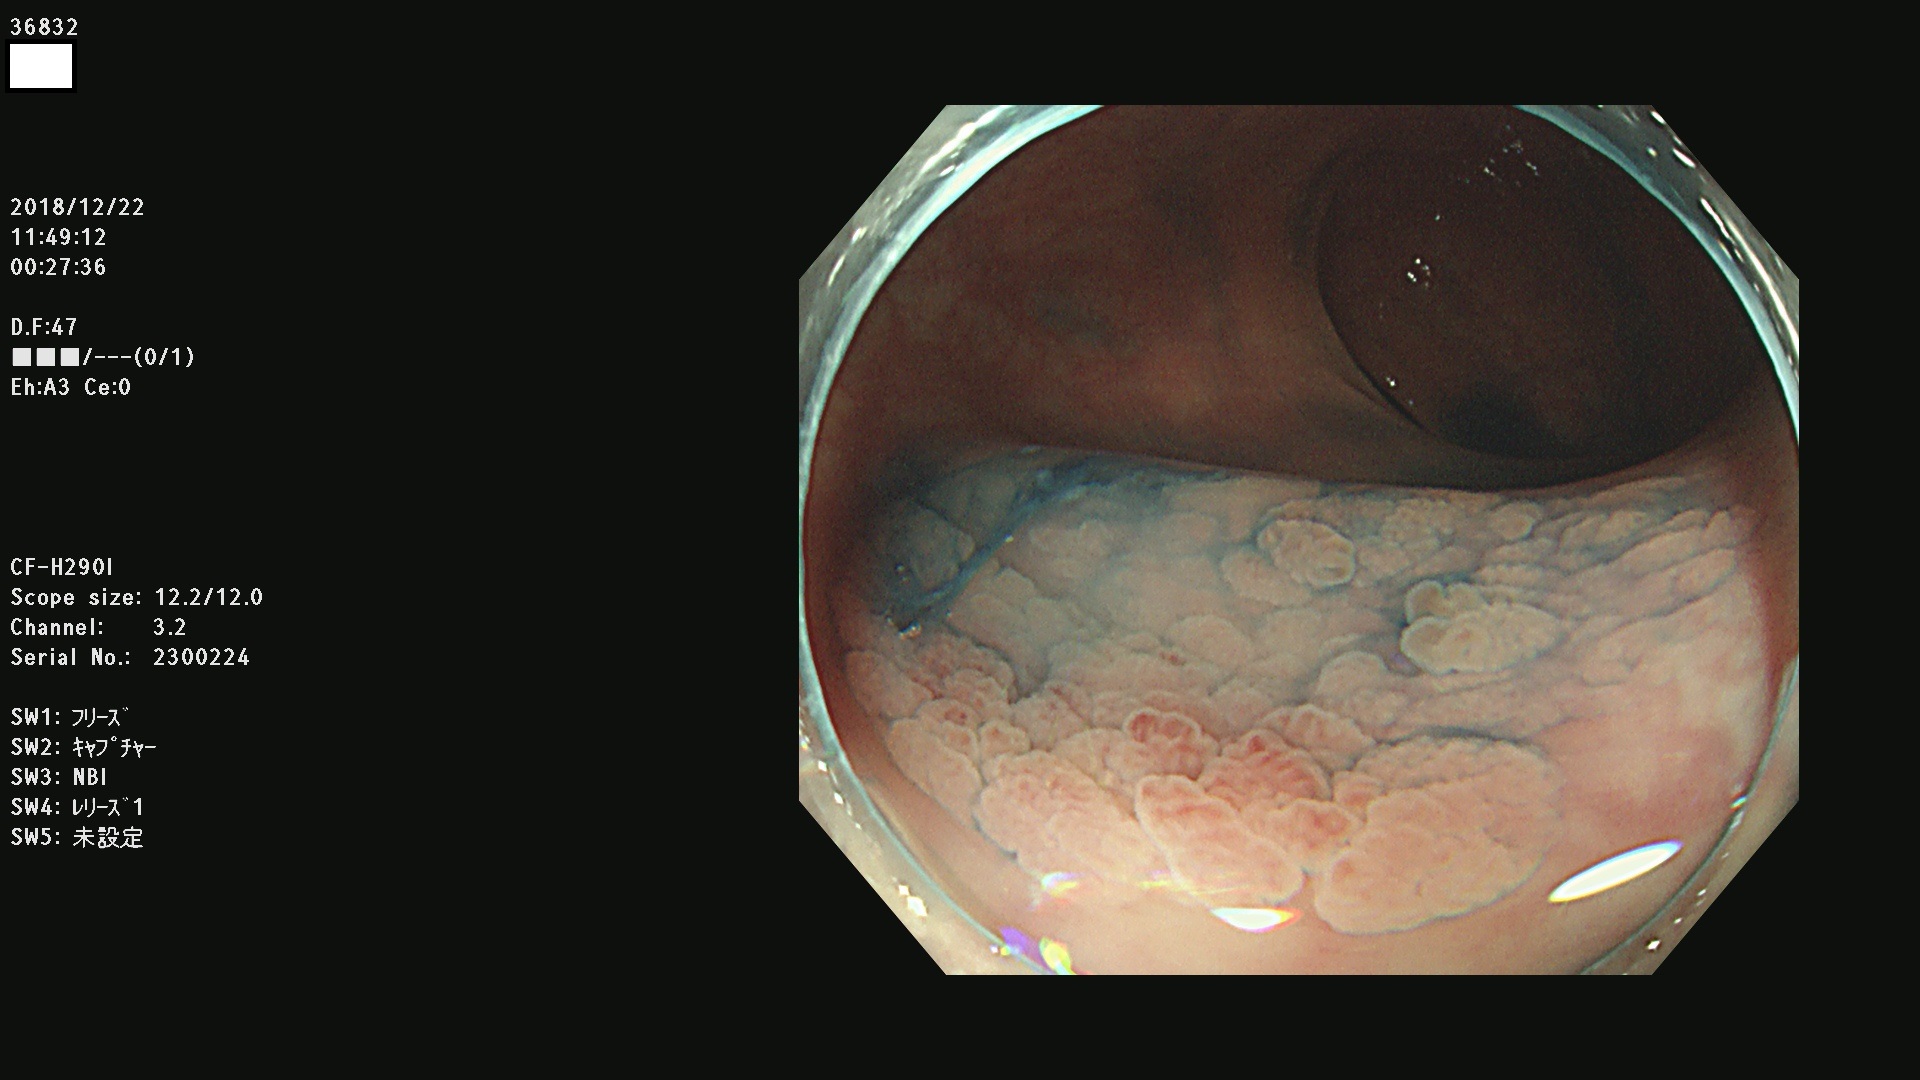

36804 36806 36807 36808 36809 36810 36811 36813 36815 36816 36817 36818 36820 36821 36822 36824 36825 36826 36828 36829 36830 36831 36832 36833 36834 36835 36837 36840 36841 36842 36845 36846 36848 36849 36851 36852 36853 36854 36855 36857 36859 36860 36861 36862(SSAPのみ) 36863 36864 36866 36868 36869 36870 36873 36875 36877 36878 36879 36881 36882 36883 36884 36885 36886 36887 36888 36889 36891 36892 36893 36894 36895 36896 36897 36898 36899

発見困難で危険性の高い平坦型病変(上記100名より抽出)